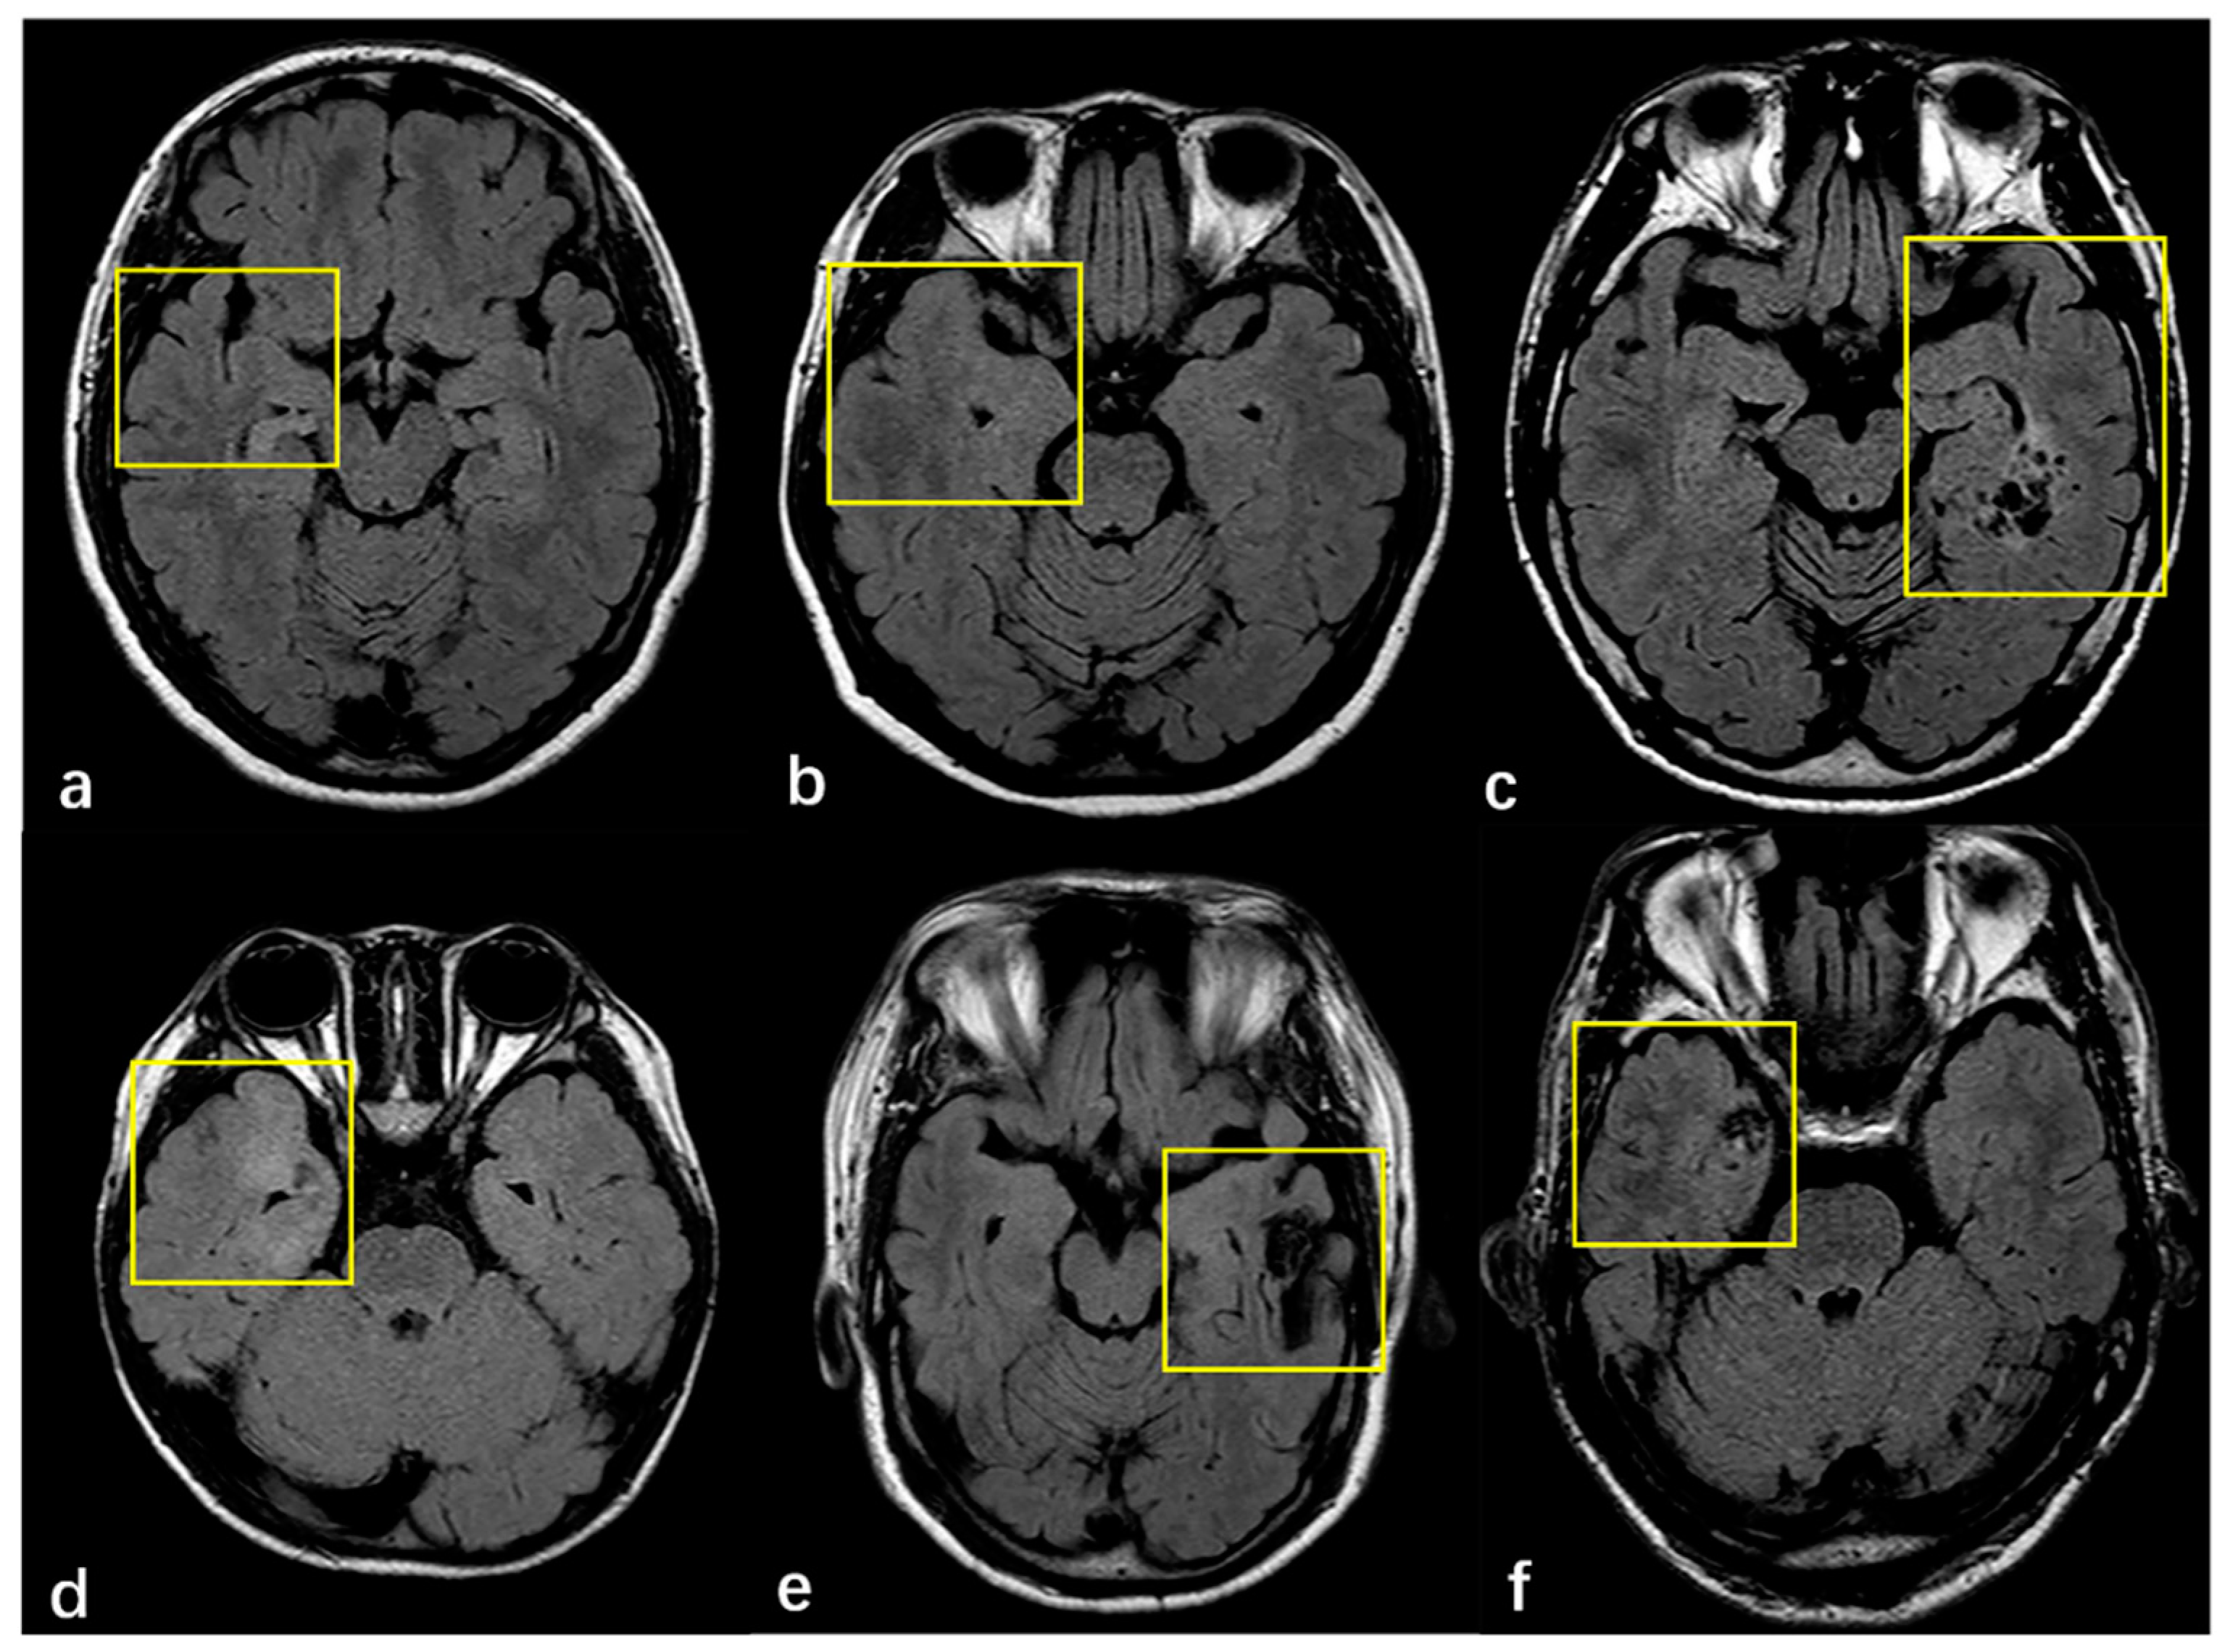

Surgical pathology findings for 266 patients with FCD type III are shown in Table 2. According to the ILAE, 183 (68.8%), 61 (22.9%) and 22 (8.3%) cases were histopathologically diagnosed with FCD Ⅲa, FCD Ⅲb and FCD Ⅲc, respectively. Thickening/atrophic cortical were detected in 90 (13.5%) patients, the indistinctness of the gray–white matter junction in 176 (66.2%) patients, hyperintensity changes in 166 (62.4%) patients, and MRI negative findings of FCD in 36 (13.5%) patients. There were 156 (58.6%) cases with two or more combinations of cortical abnormalities. For FCD type Ⅲb, 41 (67.2%) were ganglioglioma (GG), 14 (22.9%) were dysembryoplastic neuroepithelial tumor (DNT), 1(1.6%) was papillary glioneuronal tumor (PGNT), 1(1.6%) was angiocentric gliomas (AG) and 1(1.6%) was GG, complicated by DNT. FCD type Ⅲc include 15 (68.2%) cases of cerebral cavernous hemangioma malformations (CCM) and 7 (31.8%) cases of cerebral arteriovenous malformations (AVM). FCD type Ⅲa was evaluated with 183 patients, of which 15 (8.6%) cases were FCD typeⅠa, 147 (84%) cases were FCD typeⅠb and 13 (7.4%) cases were FCD typeⅠc. We also found that 5 patients (8.6%) of FCD type Ⅲb were FCD typeⅠa, 49 (84.5%) were FCD typeⅠb, and 4 (6.9%) were FCDⅠc in 62 cases. In the FCD type Ⅲc as a whole, there was 1 case of FCD typeⅠa, and 21 cases of FCD typeⅠb, accounting for 4.5% and 95.5%, respectively. MRI findings of adjacent cortex in patients with FCD type Ⅲ are shown in Figure 2.

Figure 2.

(a–f) MRI finding of adjacent cortex in patients with FCD. (a) Right hippocampal atrophy without visually adjacent cortex abnormality. (b) Right hippocampal hyperintense with the thickened cortex of ipsilateral temporal lobe. (c) GG is located medial to the left temporal lobe with a normal adjacent cortex. (d) The right temporal pole and medial temporal lobe cortex were thickened, and indistinctness of the gray–white matter junction was complicated by GG. (e) Right frontal AVM without visual alterations in the adjacent cortex. (f) There is a CCM in the right temporal lobe with adjacent cortex hyperintense and indistinctness of the gray–white matter junction.